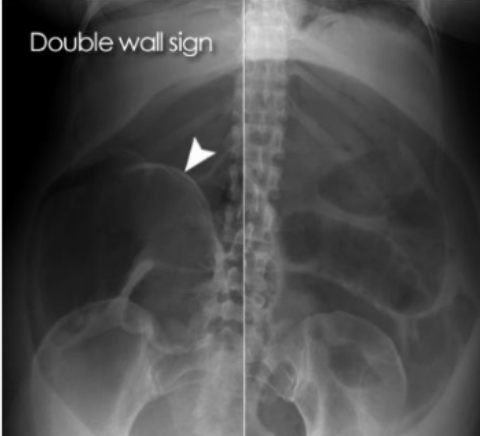

What is this and what type of scan

free air in bowel 2/2 perforated bowel, abx